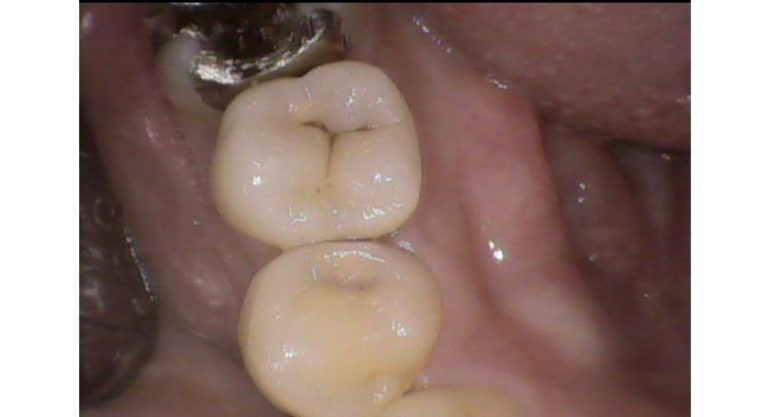

丸の部分を黒いところが問題

(虫歯の取り残し)